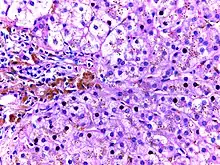

![]() | Renal cell carcinoma | Micrograph of clear cell renal cell carcinoma showing cells with clear cytoplasm, typically arranged in nests and nuclear atypia. | Category: Histopathology of renal cell carcinoma | Renal cell carcinoma |